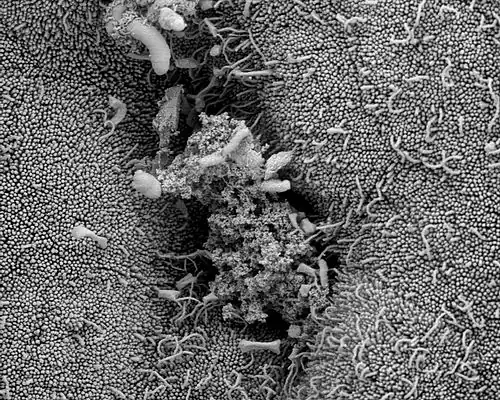

Endometrium einer Hündin mit Drüsenöffnung. REM-Aufnahme. Man beachte auch die zahlreichen Mikrovilli auf der Oberfläche der Epithelzellen.